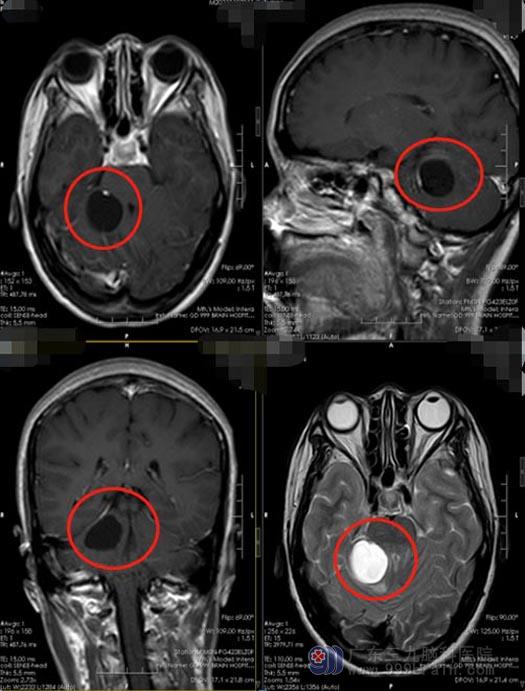

紧张的李姐和家里人通过四处打听后,来到了广东三九脑科医院,入住神经外五科。进一步头颅MRI检查显示:右侧小脑半球占位性病变:怀疑血管母细胞瘤。

血管母细胞瘤是良性、缓慢生长的中枢神经系统内的血管性肿瘤,占颅内肿瘤的1%到2.5%,成人最常见的小脑原发性肿瘤。小脑血管母细胞瘤因为发生在小脑的位置,所以会影响患者的平衡功能,如共济失调、步态不稳等;小脑前面是第四脑室,所以很容易压迫导水管而引起梗阻性脑积水,出现颅内压增高的症状,患者出现头痛、恶心、呕吐、视乳头水肿等表现。该疾病属于良性肿瘤,手术切除是主要的治疗方法。医院副院长、神经外五科主任鲁明认为患者的弥漫性脑肿胀明显,建议尽快进行手术治疗。